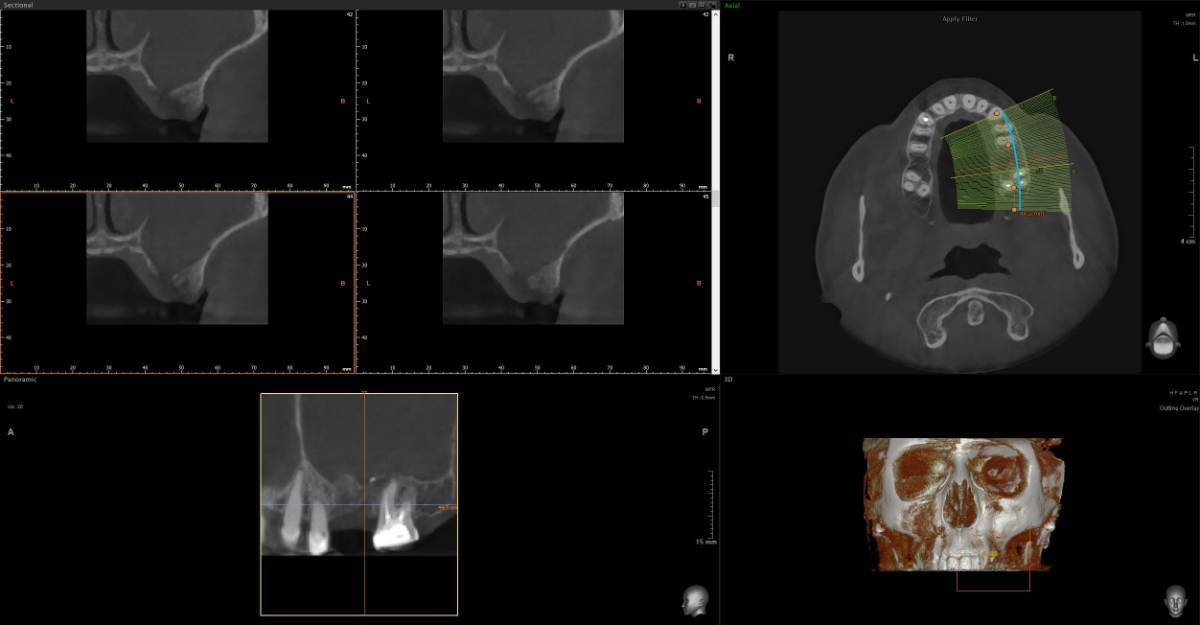

Анна1402 Опубликовано 6 марта Поделиться Опубликовано 6 марта Здравствуйте. Нужно второе мнение. Отправляю два КТ с разницей в три месяца. Первое после удаления. [🗣 «Ситуация такая: 28 ноября отошла коронка, чтобы ее снять, пришлось несколько раз ударять по зубу, решили не распиливать, чтобы сэкономить деньги. По зубу я получила около 30 или более ударов, коронку приклеили обратно, через три дня завоняло тухло. зуб пришлось удалить, была перфорация, перфорацию заложили губками и зашили, через три дня завоняло снова, в процессе этого всего два раза пропивала антибиотики. В конце Декабря хотела сдаться лорам, но так как это было перед праздниками, они меня не взяли, и сказали, что вообще операцию должен вам делать челюстно лицевой хирург, так как у меня дома младенец, я с радостью ушла и решила, буду пока справляться сама, промывала гипертоническим раствором соли, и мне стало лучше, то есть гноя у меня стало меньше, лунка у меня заросла хорошо, показывала челюстно лицевым хирургам, перфорации нет, немного стекает по задней стенке гной, но с каждым днем все меньше и пульсирует левая пазуха, правая, не скажу, что пульсирует, не болит, но были немного выделения, вопрос: на первом Кт, забита одна пазуха, и чем она забита, на втором Кт уже забиты две, хотя чувствую я себя лучше, нос у меня дышит, на первом Кт, когда я делала нос, у меня не дышал, сейчас нос у меня дышит, правая ноздря дышит, ну, вполне нормально, по сравнению с левой. Вот вопрос: делать ли операцию, можно ли ждать, и чем заполнены пазухи: гноем, отек это, или какие то инородные тела? Что это и что вы посоветуете Спойлер Вопрос: почему мне как будто лучше, а на снимке хуже. Что в пазухах? И почему правая стала тоже забита. И сдаться ли 17 марта в больницу к чхл на микрогаморотомию через губу? Заранее очень благодарю за время, которое уделите. Спасибо доктора! https://disk.yandex.ru/d/sTb5_xcHWQVHIw https://disk.yandex.ru/d/1ccGILTzDB1k0g Ссылка на комментарий

Женька Опубликовано 8 марта Поделиться Опубликовано 8 марта @Анна1402 здравствуйте, чем заполнены пазухи по снимкам сказать невозможно. Можно лишь точно сказать, что пазухи тотально затенены (в пазухах что-то есть, гной, кровь, кисты или опухоль). Соустье судя по всему не функционирует. Я бы наоборот через лоров делал. Так как не вижу никаких показаний, идти к ЧЛХ на гайморотомию. Чем делать дырки - лучше эндоскопически зайти в пазуху и санировать. Но перед этим - приём грамотного ЛОР-врача. 1 1 Ссылка на комментарий